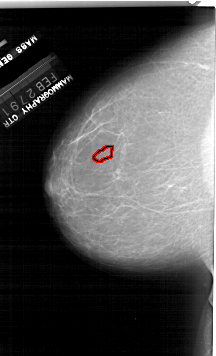

A_1916_1.LEFT_CC

LEFT_CC LINES 6406 PIXELS_PER_LINE 3886 BITS_PER_PIXEL 12 RESOLUTION 43.5 OVERLAY

FILE: A_1916_1.LEFT_CC.OVERLAY

TOTAL_ABNORMALITIES 1

ABNORMALITY 1

LESION_TYPE CALCIFICATION TYPE PUNCTATE DISTRIBUTION CLUSTERED

ASSESSMENT 4

SUBTLETY 1

PATHOLOGY BENIGN

TOTAL_OUTLINES 1